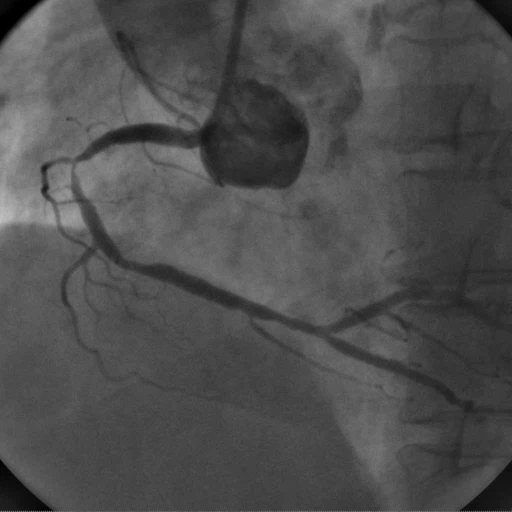

협심증, 심근경색을 진단하는 가장 정밀한 검사로 카테터라고 불리는 직경이 가는 플라스틱관(직경 2mm, 길이 약 1~2m)을 손목(요골동맥)이나 사타구니(대퇴동맥)를 통해 삽입하여 심장에 도달시킨 뒤 관상동맥 조영제를 주사하고, X-선을 이용하여 촬영하게 됩니다. 이를 통해 관상동맥의 비정상적인 구조나 폐색, 협착 부위를 확인하고, 약물치료나 경피적 관상동맥 중재술 또는 관상동맥우회술 등의 치료방향을 결정하게 됩니다.